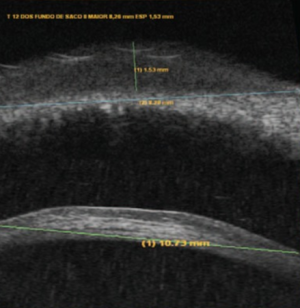

Ultrasound biomicroscopy may be performed to confirm lesion depth and diameter (Fig. 2).[7] On optical coherence tomography (OCT), the tumor presents as a homogeneous, hyporeflective lesion with thin overlying epithelium (Fig. 3).[2]